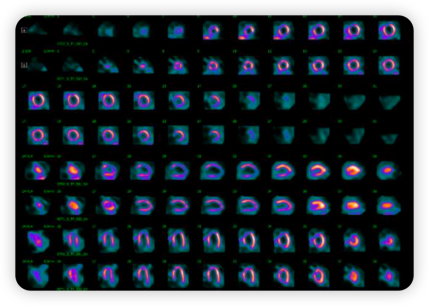

Tice医生团队最初决定先进行无创的运动负荷试验,以客观评估患者的心肌缺血情况。因此患者接受了核素心肌灌注显像(SPECT)。

检查结果显示:前壁中段至心尖部存在一个非常大的可逆性灌注缺损,伴有显著的可逆性改变,高度提示心肌缺血。此外,患者还出现了明显的短暂性缺血性心脏扩张(图1)。

图1.患者的核素心肌灌注显像(SPECT)结果